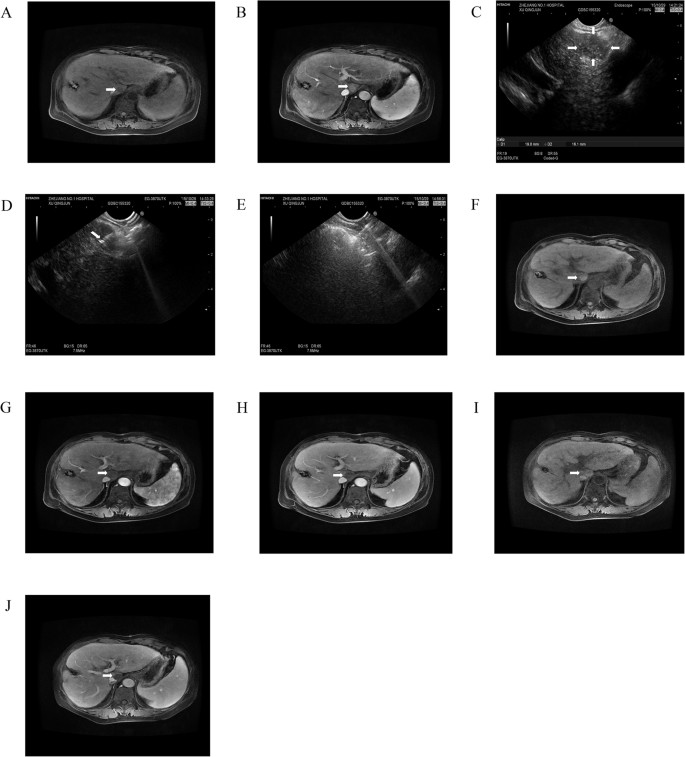

EUS-guided anhydrous ethanol ablation for lesions in liver caudate lobe.

MRI imaging in liver caudate lobe showed a lesion of low T1 signal intensity (A) (arrowhead) and significant enhancement in arterial phase (B) (arrowhead). (C) at liver caudate lobe EUS scan showed a well-defined hypoechoic 1.9*1.6 cm lesion (arrows). (D) It indicated that 22G biopsy needle with EUS guidance was inserted into the lesion along with the needle sheath (arrowhead), and (E) diffuse increase in echogenicity covering the whole mass after the percutaneously punctured injection of anhydrous alcohol. After 1 month follow-up, MR scan was seen high T1-weighted signal intensity (F) (arrowhead) and no obvious enhancement during arterial (G) (arrowhead) and substance phase (H) (arrowhead). After 15 months follow-up, it showed high T1-weighted signal intensity (I) (arrowhead) and contrast material-enhanced MR images showed completed ablation without enhanced lesions (J) (arrowhead).

All patients were followed up for 1–2.5 years as scheduled. At 12 months after treatment, 12 of 13 (92.3%) patients achieved complete tumor response in iodine-125 particle implantation (Fig. 1) while 3 of 10 (30%) in anhydrous ethanol ablation (Fig. 3 and Table 4). Residual tumor was detected in 8 patients after anhydrous ethanol ablation (n = 2) or iodine-125 particle implantation (n = 6); these patients were further treated with second-look EUS-guided interventional treatment (n = 5) and radiotherapy (n = 2) and surgical resection (n = 1). Complete response was achieved after again EUS-guided treatment in 3 of 5 patients, whereas the remaining 2 patients required surgical resection but only one succeed. Recurrence was observed in 2 patients at 1 year after anhydrous ethanol ablation. No clinically significant late-onset complications occurred.